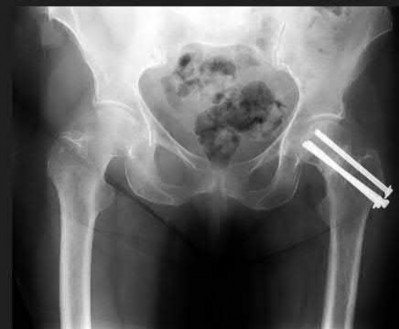

A 76-year-old male community ambulatory presented to clinic complaining of pain in the left groin that has been persistent for the last 8 months. Radiographs obtained from clinic are seen in Figure A. You suspect a femoral neck nonunion and obtain a CT scan which confirmed it. Which of the following statements is true?

Figure A is an AP pelvic radiograph demonstrating a nonunion of a femoral neck fracture after suboptimal fixation with 3 cannulated screws in a triangle configuration.

Illustration A is an AP radiograph of the left hip in this patient following conversion to THA.

Figures and Illustrations: